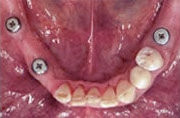

3 Implantate als Basis eingesetzt

Schematischer Unterkiefer mit 3 Schraubimplantaten

Fehlen mehrere Zähne, so spricht man vom teilbezahnten Kiefer. Solche größeren Zahnlücken konnten früher oftmals nur mit herausnehmbaren Teilprothesen geschlossen werden, wenn eine Brückenversorgung nicht mehr möglich war. Implantate erlauben, die Lücke mit einer implantatgetragenen festsitzenden Brücke zu schließen, ohne herausnehmbare Prothesen und ohne Abschleifen gesunder Nachbarzähne.